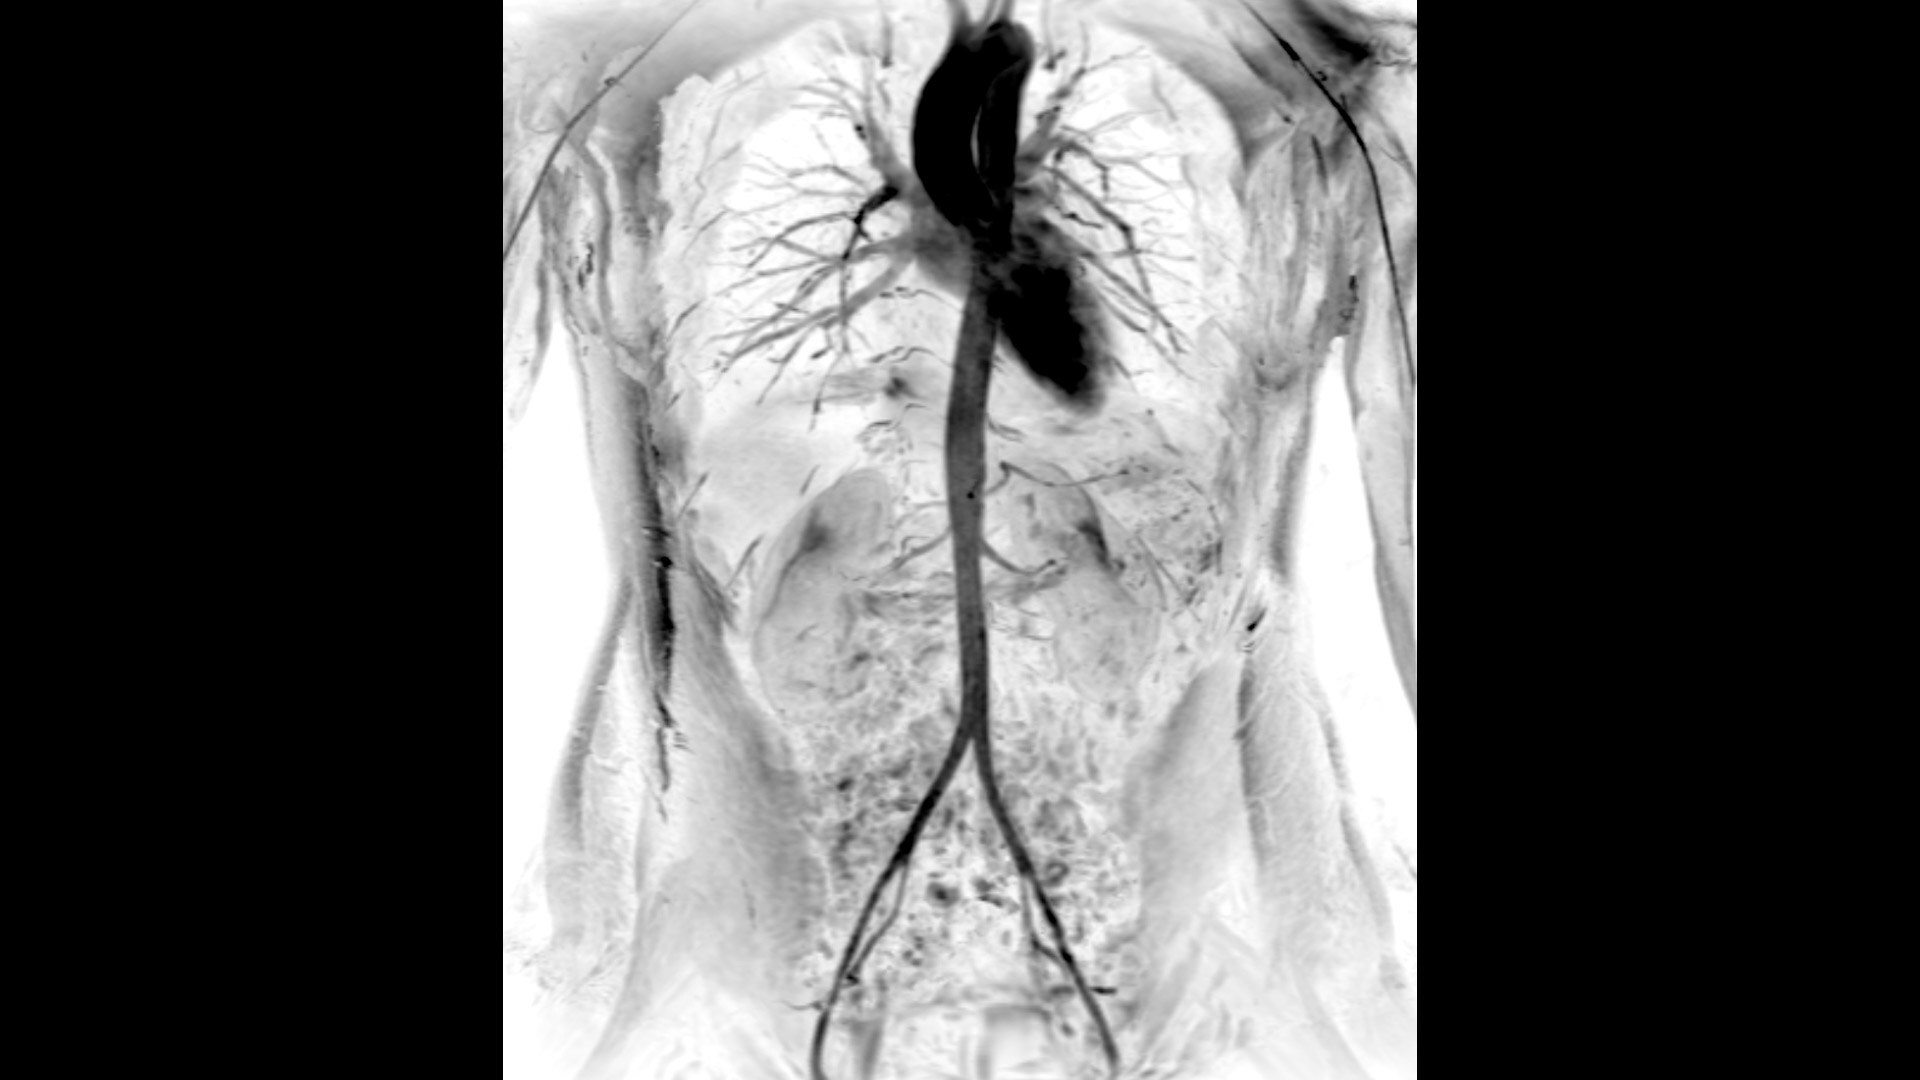

An award-winning industry first in MRI coils. With overlapping, ultra-light, flexible coil elements at their heart, AIR™ Coils deliver an MRI experience that gets closer to your patient, so you get closer to the truth. Representing a new standard in MRI coil technology, AIR™ Coils enable a simplified, faster workflow while maintaining excellent image quality. Scan complex anatomies and complicated conditions in a variety of patient sizes with exceptional results.

The shape of the MRI coil no longer determines what you can do with it. Wrap it around a knee for a complete knee image. Drape it over the patient's body. With an adaptive AIR™ Coil that is light, form fitting and easy to position, it’s the closest you can get to total positioning freedom with 360-degree coverage.

• 360 degrees of coverage for MSK imaging

• Positioning freedom with previously hard-to-scan anatomies